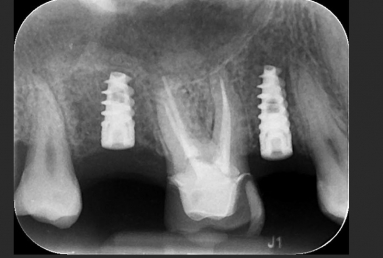

Dental implants upper second premolar, upper second molar